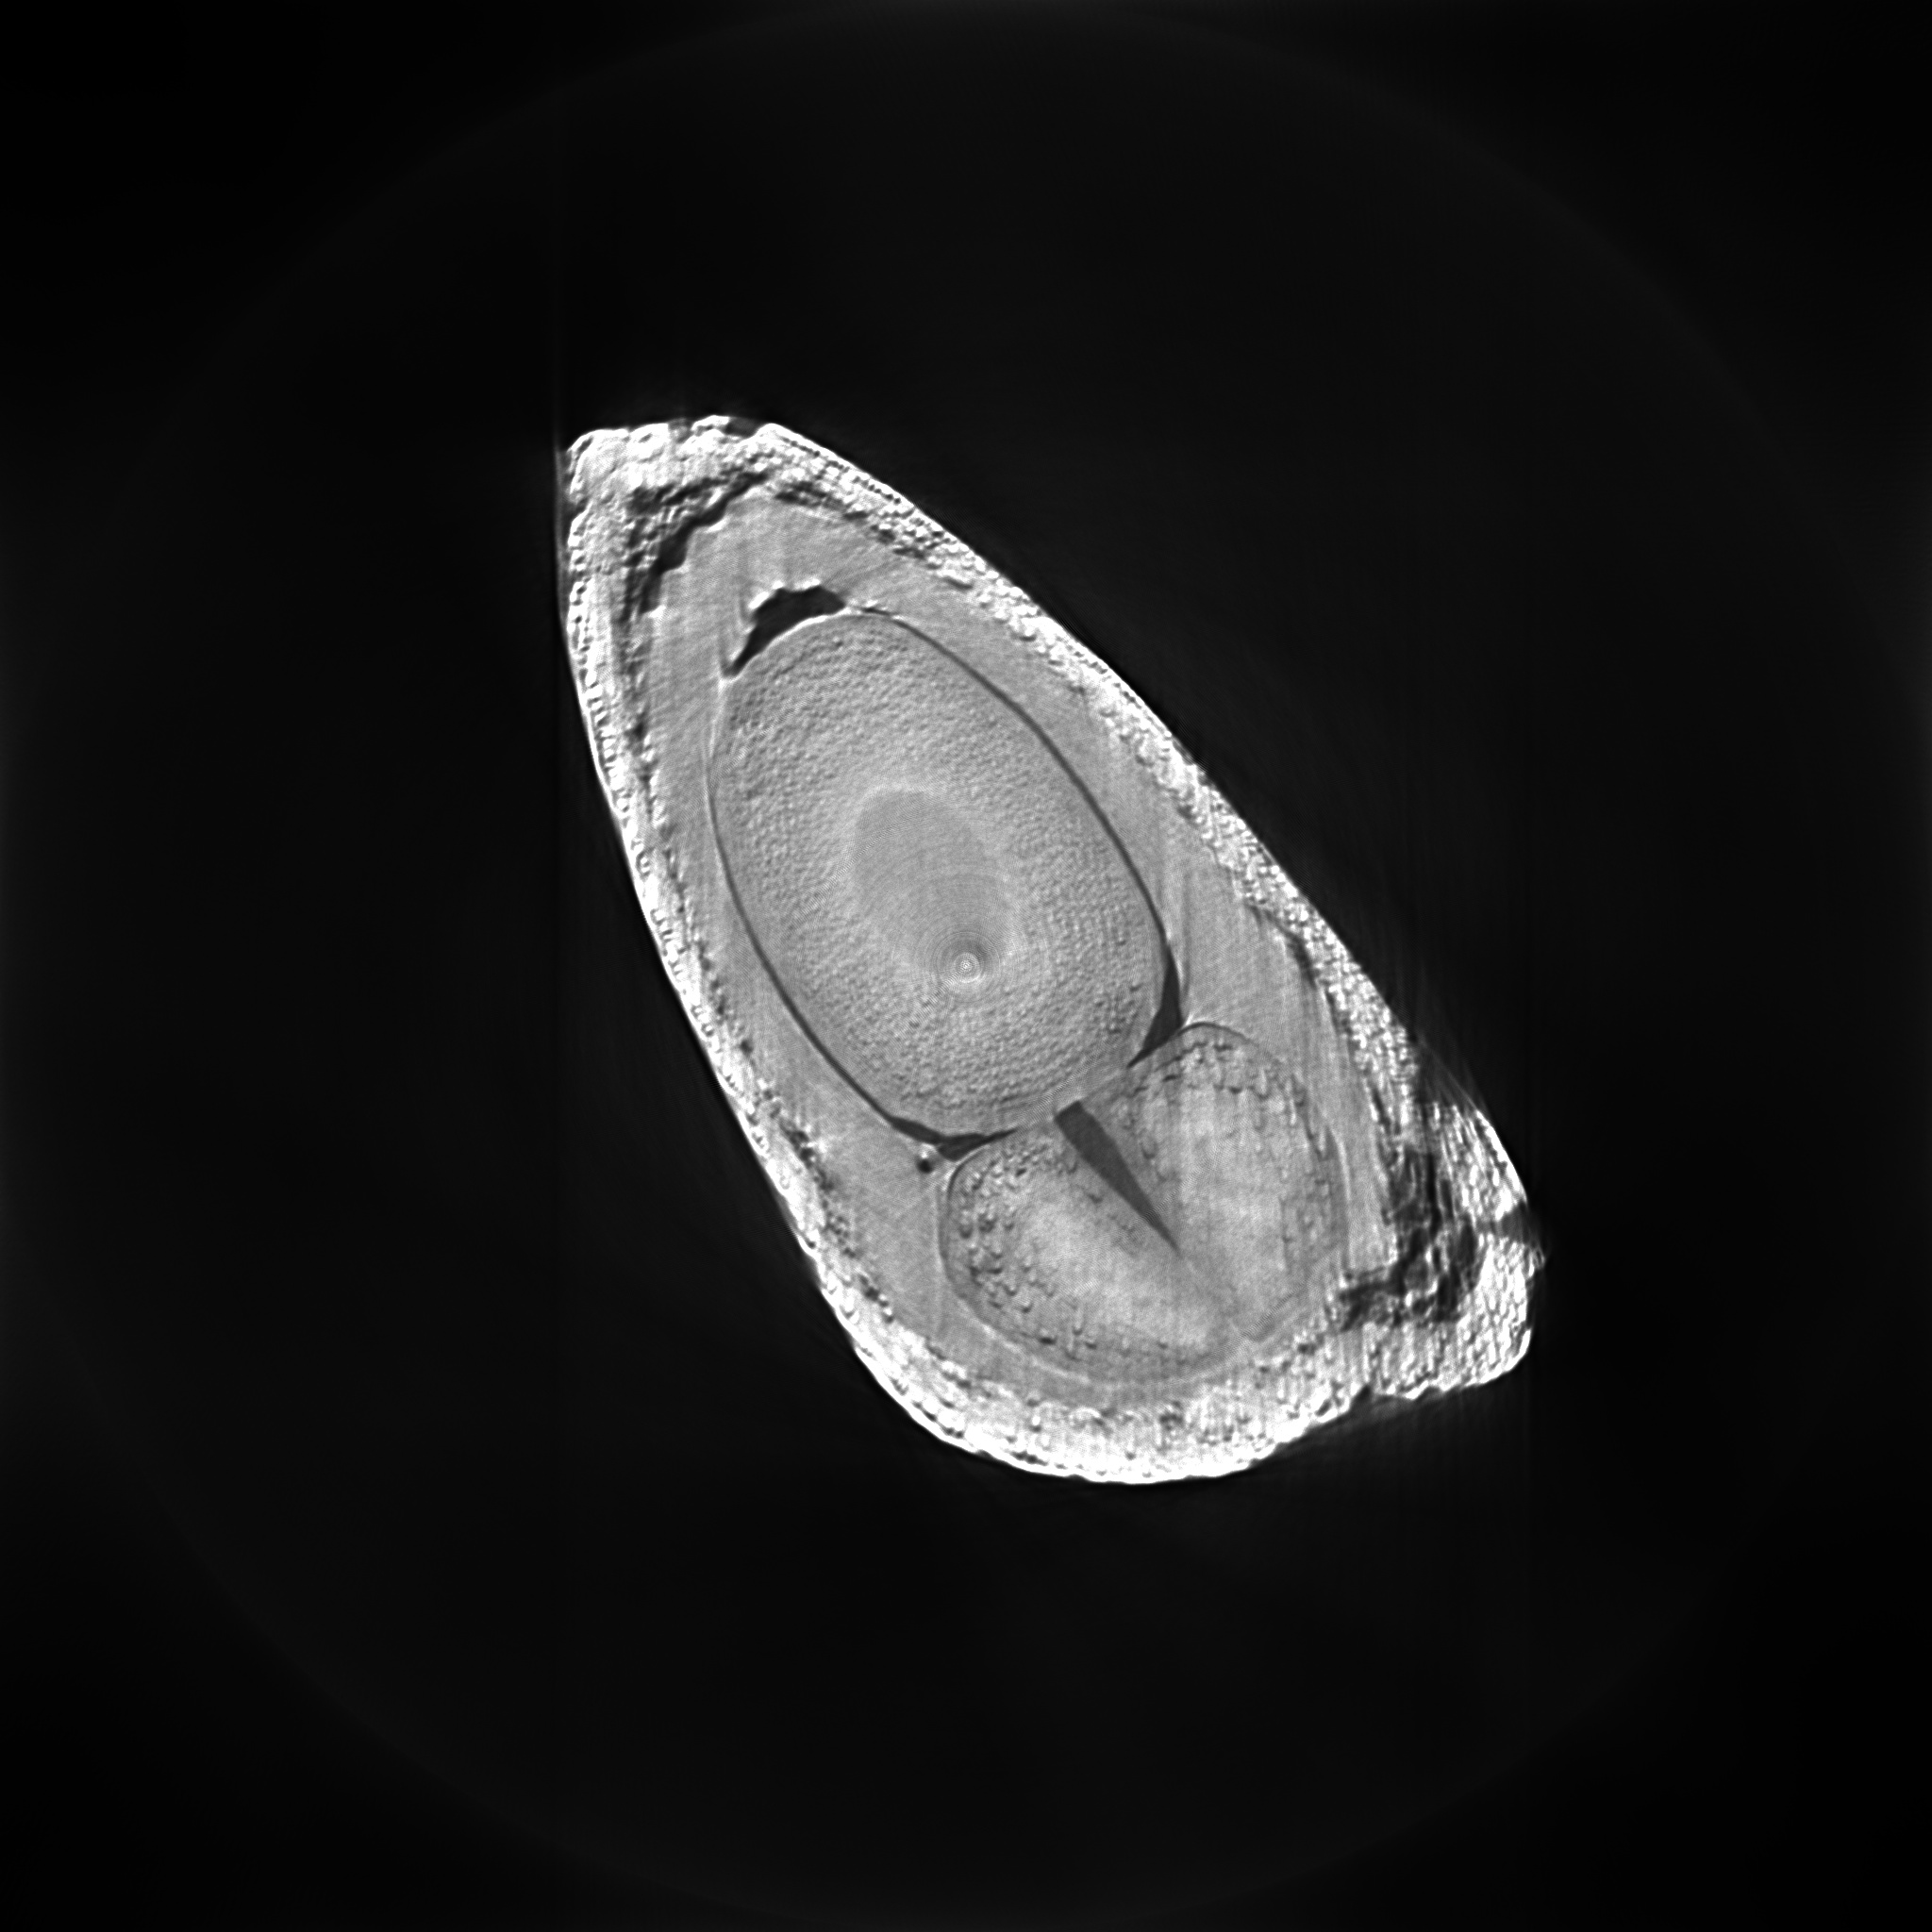

Data for this set of experiments was obtained at the Imaging Beamline (imx) of the Brazilian National Synchrotron Light Source (lnls) through illumination of an apple seed by x-rays. Each radiographic image was pixels in size and the sample was rotated by between each of the images, thereby totaling, for each slice to be reconstructed, views times rays of tomographic count data . Reconstructed images have dimensions of pixels.

The graphic on the right of Figure 5 displays plots of the objective function value versus total variation for the iterates of each method. The curves make clear that the superiorized version of the algorihtms always present the better compromise between data adhesion and smoothness when compared to its respective non-superiorized version. Figure 6 shows how this property translates to better image quality in practice. The lower row of Figure 6 shows isocontours overlaid on top of details of the images, in order to show that the superiorized image is noticeably smoother, therefore potentially more useful for visualization tasks. If, on the other hand, some apparent detail seems to have been removed from the image, part of these fine details may be reconstruction artifacts but we make no claims in this direction. Notice that these results are in accordance with those obtained using saem and its superiorized versions presented before.

We are grateful to lnls for providing the beamtime for the acquisition of tomographic data for the apple seed reconstruction experiments.